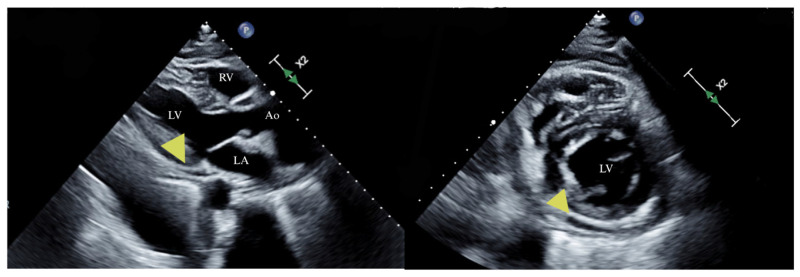

伊鲁替尼,一种布鲁顿酪氨酸激酶抑制剂,已经改变了各种血液系统恶性肿瘤的管理。然而,它与心血管毒性,特别是心房颤动(AF)、高血压和心力衰竭(HF)的关联引起了临床关注。心包积液虽然罕见,但也是一种值得注意的新并发症。我们报告一个62岁男性淋巴浆细胞性淋巴瘤的病例,最初用苯达莫司汀和利妥昔单抗治疗,由于明显的中性粒细胞减少而停止治疗。开始伊鲁替尼治疗,3个月时部分缓解。伊鲁替尼治疗约10个月后,患者出现新发呼吸困难、心悸和头晕。心电图显示房颤伴心室快速反应,经胸超声心动图(TTE)显示左心室射血分数降低40%,心包积液中度。使用依鲁替尼之前的基线评估显示心脏功能正常。考虑到心力衰竭伴射血分数降低和心包积液的发展,停用依鲁替尼。患者开始接受指南指导的心力衰竭药物治疗。6个月后,患者表现出明显的心脏恢复,射血分数恢复正常,心包积液消失。虽然心房颤动和心力衰竭被认为是依鲁替尼的不良反应,但心包积液很少被报道。鉴于伊鲁替尼的使用日益增加,临床医生应对心血管并发症保持警惕。早期识别和管理对于降低与这些不良反应相关的发病率和死亡率至关重要。该病例强调了对接受伊鲁替尼治疗的患者进行全面心血管监测的重要性,并有助于越来越多的关于其心脏毒性的文献。

Ibrutinib, a Bruton's tyrosine kinase inhibitor, has transformed the management of various hematological malignancies. However, its association with cardiovascular toxicities, particularly atrial fibrillation (AF), hypertension, and heart failure (HF), has raised clinical concerns. Pericardial effusion, though rare, is an emerging complication warranting attention. We present the case of a 62-year-old male with lymphoplasmacytic lymphoma, initially treated with Bendamustine and Rituximab, which was discontinued due to significant neutropenia. Ibrutinib therapy was initiated, leading to a partial response at three months. Approximately ten months into ibrutinib treatment, the patient developed new-onset dyspnea, palpitations, and dizziness. ECG revealed AF with rapid ventricular response, and transthoracic echocardiogram (TTE) showed a reduced left ventricular ejection fraction of 40 % and a moderate pericardial effusion. Baseline assessments prior to ibrutinib had indicated normal cardiac function. Given the development of heart failure with reduced ejection fraction and pericardial effusion, ibrutinib was discontinued. The patient was initiated on guideline-directed medical therapy for heart failure. Over six months, the patient exhibited significant cardiac recovery, with normalization of ejection fraction and resolution of the pericardial effusion. While atrial fibrillation and heart failure are recognized as adverse effects of ibrutinib, pericardial effusion is less commonly reported. Given the increasing use of ibrutinib, clinicians should maintain vigilance for cardiovascular complications. Early recognition and management are crucial to mitigate morbidity and mortality associated with these adverse effects. This case highlights the importance of comprehensive cardiovascular monitoring in patients receiving ibrutinib and contributes to the growing body of literature on its cardiotoxic profile.